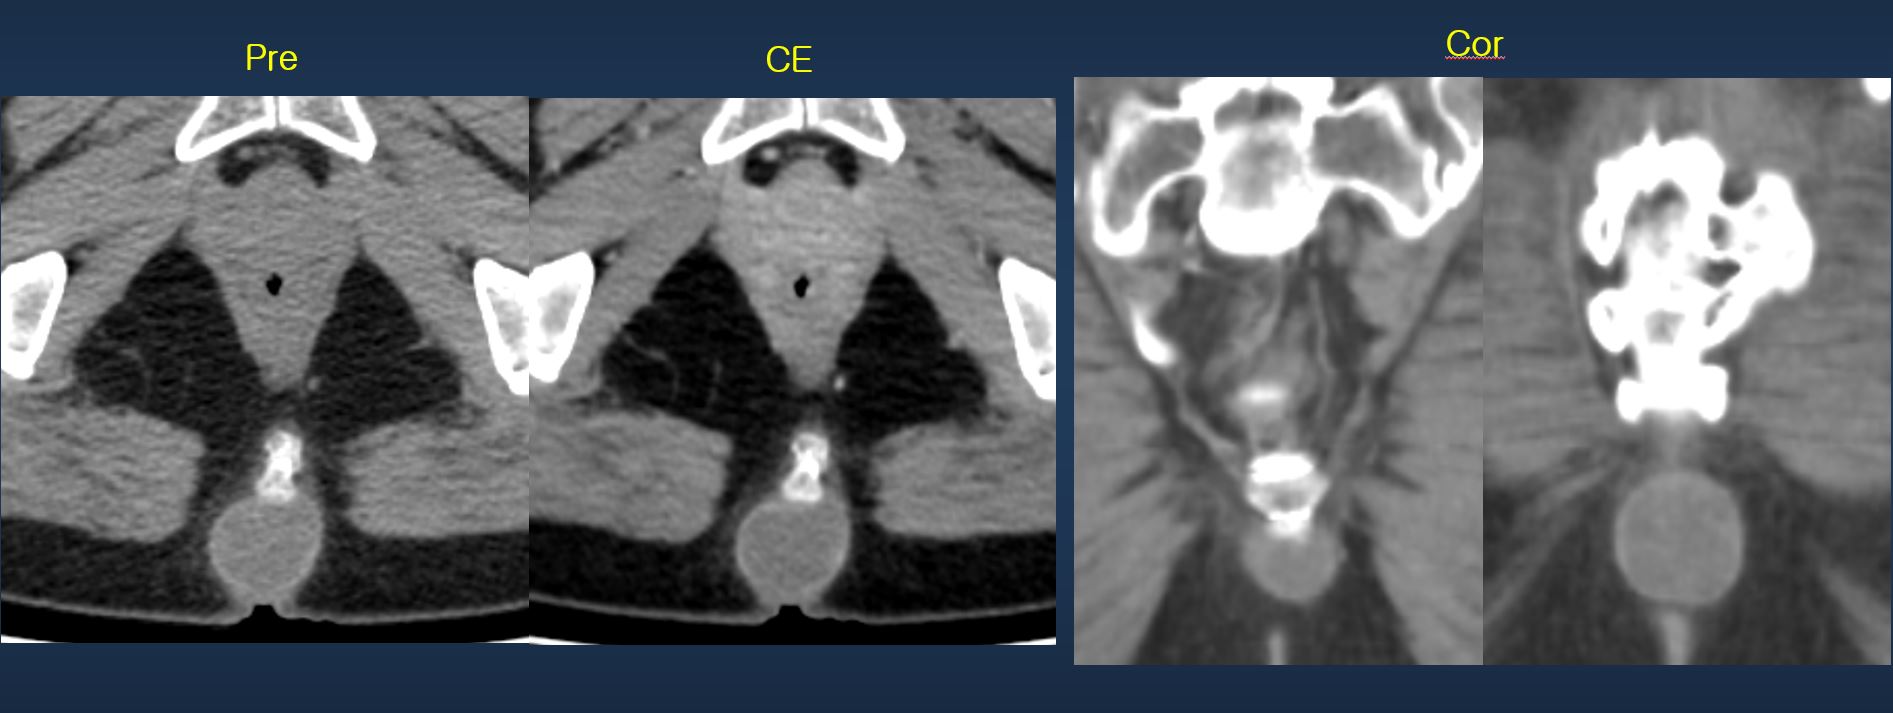

Palpable retrococcygeal lesion

ABDOMEN

Sunyoung Lee

Severance Hospi...

742

2026-01-31